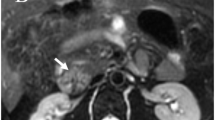

Although the drop-out rate due to positioning artefacts was low in our patients (2/38), it has to be emphasized that with any image fusion technique, supervision of results and control of plausibility remain crucial (Fig. 1).

Original and fused images from a 62-year-old male patient after resection of the pancreatic primary, right-sided hemihepatectomy and enucleation of liver metastases. The CT scan is shown on the left, the corresponding SPET image in the centre and the fused image on the right. The current SRS-SPET showed a focus suspected to be a hepatic lesion. For further clarification of the localization, image fusion was performed. However, as physiological accumulation in the right kidney was partially projected into the thorax according to the corresponding CT scan, this registration was considered to be invalid for evaluation and the patient was excluded from the study. Alterations of the patient’s breathing pattern and the resulting changes in diaphragmatic excursions or different positioning of the patient were considered as possible reasons for this unsuccessful image fusion